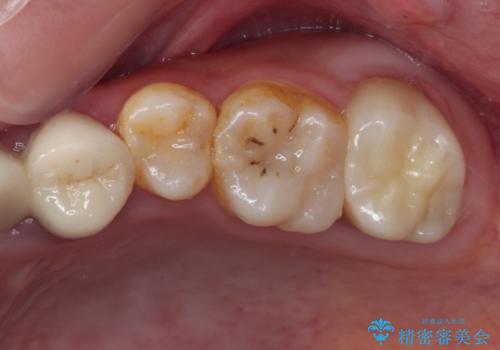

[ インプラント治療 ]失った奥歯を回復したい

![[ インプラント治療 ]失った奥歯を回復したいの症例 治療後](https://seimitsushinbi.jp/wp/wp-content/uploads/2021/11/7d51b0ec04f819febabdd26c9bfb7954-500x350.jpg?v=1637928867)